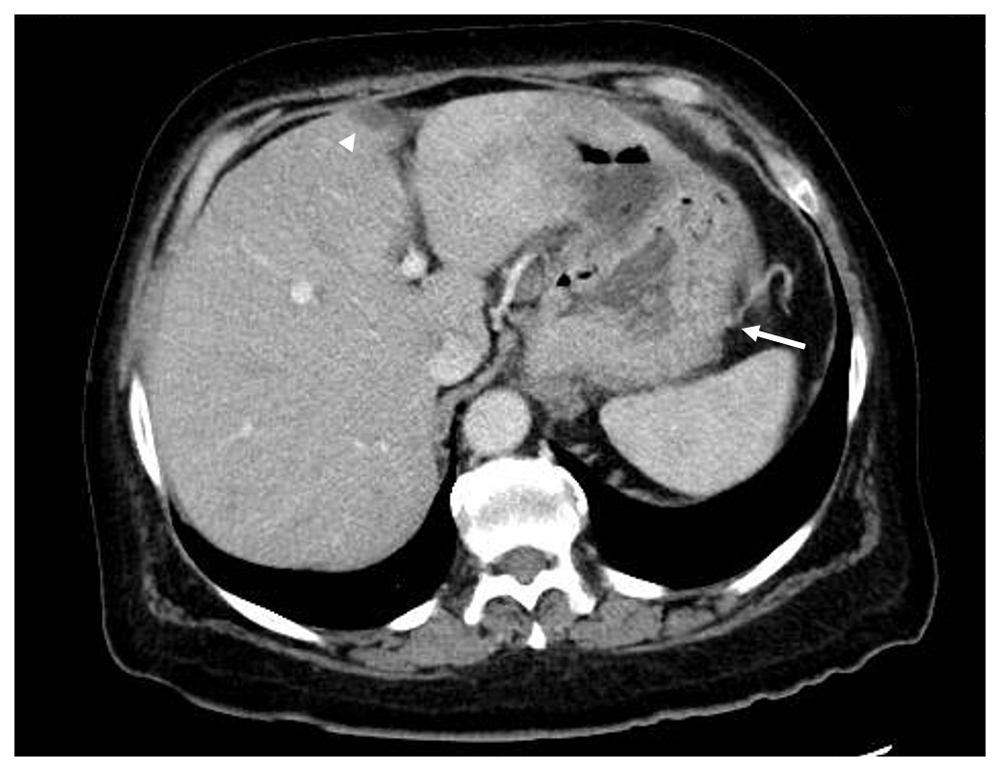

Vital signs and measurements were unremarkable. A detailed physical examination was nonrevealing. Serum laboratory analysis was notable for a significant anemia, as well as a low vitamin B12 and iron deficiency (Table 1). She was urgently managed with a restrictive transfusion strategy by one unit of leukoreduced packed red blood cells, which improved her symptoms and hemoglobin. Abdominopelvic imaging was obtained by computerized tomography (CT) scans with contrast, which were primarily equivocal (Figure 1). Subsequently, she underwent esophagogastroduodenoscopy (EGD) for further evaluation. Esophageal findings included moderate esophagitis and salmon-colored mucosa at the gastroesophageal junction suggestive of Barrett's esophagus. Beyond the esophagus, a large 7-cm hiatal hernia was evident. An extensive, deep ulcer was noted to involve the entirety of the incisura and pre-pyloric area, as well as extended along the lesser curvature (Figure 2). Multiple biopsies of the ulcer were obtained to evaluate for malignancy, as well as random gastric biopsies to evaluate for Helicobacter pylori colonization. Helicobacter pylori immunohistochemical (IHC) stain was ultimately negative. Due to the tumor's size, gross appearance, ulcerations, and bleeding erosions noted on EGD a malignant process was suspected. Based on the suspicions for an underlying malignant gastric neoplasm and the presence of a vitamin B12 deficiency, serum serologic testing for PA was obtained. Laboratory testing was positive for anti-IF confirming the diagnosis of PA (Table 1).

Nonspecific gastric fold thickening in the fundus is observed (arrow). An incidental finding in the liver was noted by a small focal hypoattenuation in the middle segment of the left lobe of the liver adjacent to the fissure for ligamentum teres (arrowhead). This nodule was confirmed as PET-negative on later PET/CT studies.